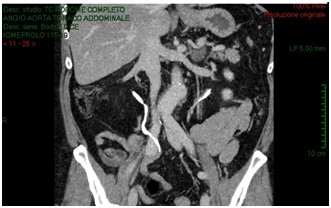

The CT-scan, targeted to a suspect of hemorrhage, did not have delayed phases. Patient received paracentesis with around 3200 cc fluid drained that was sent to microbiological examination. Result of bacteriological exam revealed infection by Proteus Mirabilis and he received target antibiotic therapy with resolution of septic status. In XXII post-operative day, for a progressive increase of serum creatinine we decided to perform an Uro-CT scan. The exam showed reduction of intraperitoneal fluid, right iliac side fluid collection with contrast enhancement during delayed phases; right ureter was not visible under fluid collection (Figure 3). We attempted to insert a ureteral stent in retrograde way but ureter resulted totally interrupted inside the fluid collection so the patient was undergone to explorative laparotomy and toilette of fluid collections. We found ureteral loss of substance of around 3 centimeter localized in anterior ureteral wall. We manufactured end-to-end ureteral anastomosis after positioning of ureteral stent seven French. We removed ureteral stent after 3 months and currently the patient is in follow-up with a good renal function as shown at last CT-scan after 10 months (Figure 4).

Figure 2: CT-scan shows increasing of intra-retroperitoneal fluid with small bowel and right colon compression and increase of right iliac region serous-hematic fluid.